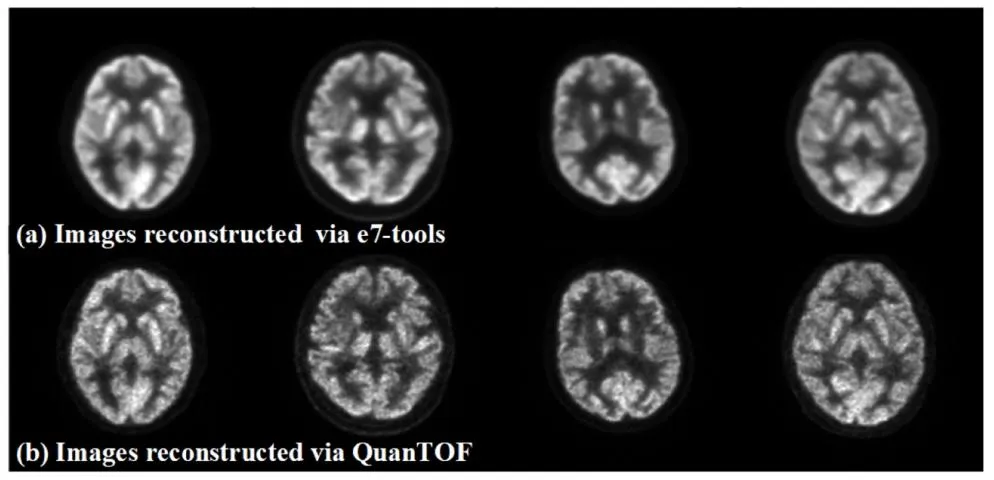

In this study, 1224 head scan datasets were acquired using a Siemens Biograph Vision PET/CT scanner. The raw list-mode datasets were reconstructed using QuanTOF (Yuan et al., 2024), a GPU-accelerated, Bayesian penalized likelihood reconstruction algorithm. QuanTOF integrates time-of-flight (TOF) information and complete correction techniques, ensuring high-quality PET image reconstruction. To simulate low-dose PET conditions, images were reconstructed from scan shortened durations of 30, 12, and 5 s, corresponding to ¼, ⅒, and 1/24 of the full dose, respectively, with 120 s of scan data serving as the full-dose reference. As illustrated in Fig. 1, the reconstructed images via QuanTOF using list-mode datasets, due to accurate modeling of imaging physics, exhibit clearer details and sharper edges compared to those reconstructed via the vendor’s e7-tools solution using sinogram datasets, providing a more reliable assessment of the model’s ability to preserve fine details.

2.1 PET图像重建 本研究使用西门子Biograph Vision PET/CT扫描仪采集了1224例头部扫描数据集。原始列表模式数据集通过QuanTOF算法(Yuan等,2024)进行重建,该算法是一种基于GPU加速的贝叶斯惩罚似然重建算法。QuanTOF整合了飞行时间(TOF)信息和完整的校正技术,确保了高质量的PET图像重建。为模拟低剂量PET场景,研究从缩短至30秒、12秒和5秒的扫描时长中重建图像,分别对应全剂量的¼、⅒和1/24,以120秒的扫描数据作为全剂量参考。如图1所示,基于列表模式数据集通过QuanTOF重建的图像,由于对成像物理过程的精确建模,与通过厂商e7-tools方案基于正弦图数据集重建的图像相比,细节更清晰、边缘更锐利,为评估模型保留精细细节的能力提供了更可靠的依据。

Fig. 1. Images reconstructed by e7-tools (top row) and QuanTOF (bottom row).

图1 分别通过e7-tools(上行)和QuanTOF(下行)重建的图像。